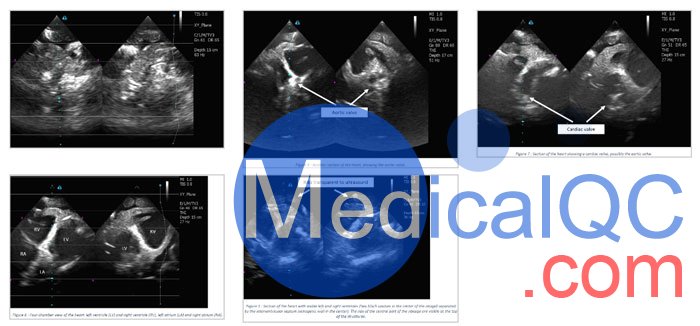

HT-A01心脏超声模体是健康成人心脏的逼真模拟器。该模型与 X 射线/CT、超声波和 MRI 兼容。该产品具有广泛的应用范围,因为它还具有支持跳动功能和产生逼真的运动的潜力。它的一些用途和应用包括经食管和经胸超声心动图、超声导航内窥镜检查、超声探头下的导管插入、血管造影和其他基于心脏的研究和开发研究。

注意:本产品配有水箱,如上图所示。水箱可帮助研究人员正确安装心脏,并在内部结构和心脏运动的视图方面实现模体的正确性能。

HT-A01成人心脏模体,HT-A01心脏超声模体解剖学特征:

2 个心房,2 个心室:

4 阀门